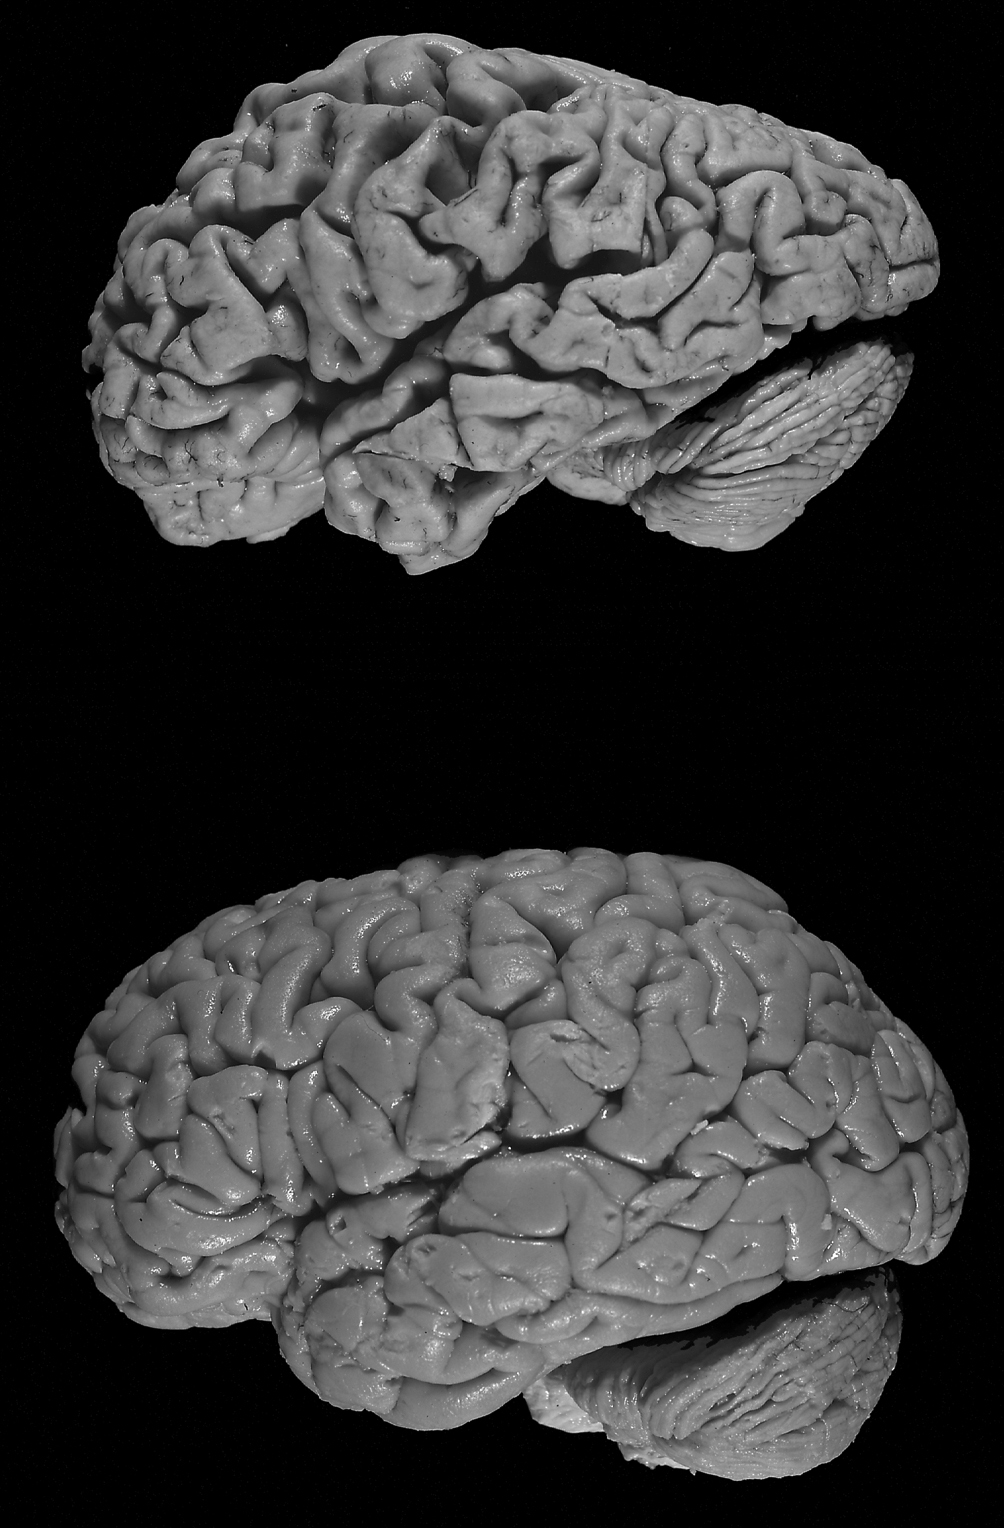

Le cerveau d’Auguste est très abîmé. Certaines zones sont atrophiées et d’étranges dépôts sont visibles… Aloïs Alzheimer observe pour la première fois les lésions anatomiques de la maladie qui porte désormais son nom. La maladie d’Alzheimer est une maladie dite "neurodégénérative". Certaines cellules du cerveau, les neurones, s’abîment et meurent progressivement. En particulier, dans la zone responsable de la mémorisation : l’hippocampe.

Cette destruction est due à la présence, en trop grande quantité, de deux protéines : Tau et bêta-amyloïde. À l’intérieur des neurones, l’accumulation de la protéine Tau perturbe le fonctionnement normal de la cellule en bloquant les messages qui y circulent. À l’extérieur, les protéines bêta-amyloïdes s’agrègent pour former des "plaques séniles" qui grossissent entre les neurones et les écrasent. Résultat : les neurones finissent par mourir…